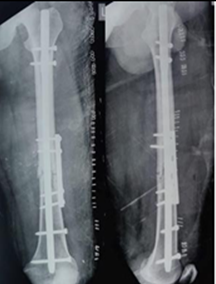

None of the patients experienced post-operative knee or hip stiffness after undergoing combination fixation with an intramedullary nail and derotation plate. X-rays of the patient with follow-ups at 3 months and 6 months(Fig. 1, 2, 3, 4).

Figure 3: POD 3-month X-rays.